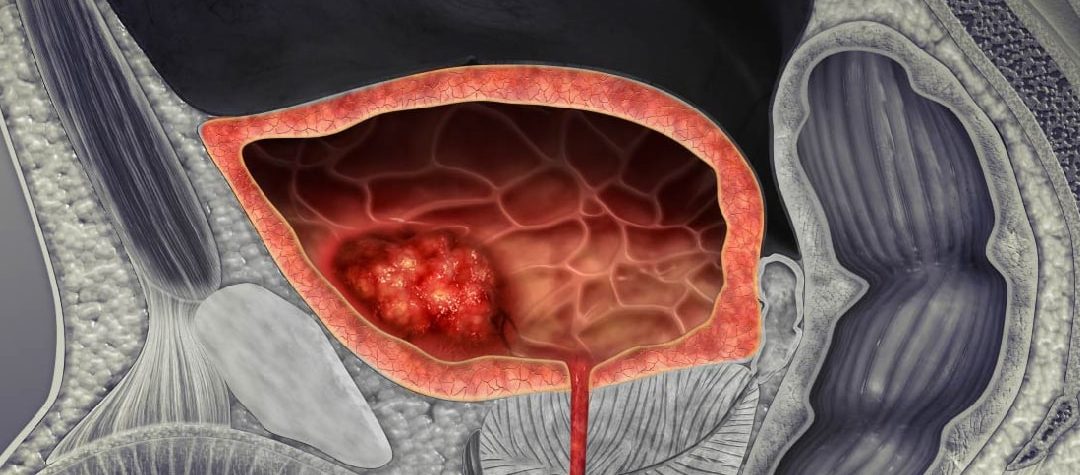

Eficacia y seguridad de los inhibidores de los receptores de andrógenos para el tratamiento del cáncer de próstata avanzado

Este metanálisis en red indica que no existe un inhibidor del receptor de andrógenos (IRA) que alcance los objetivos terapéuticos más eficaces y más seguros para el tratamiento del cáncer de próstata avanzado, ya que existe un compromiso entre la eficacia y la seguridad de los IRA en este contexto. Los médicos deben sopesar los riesgos para la seguridad frente a los beneficios previstos al recetar estos medicamentos. British Journal of Clinical Pharmacology, 11 de julio de 2024.